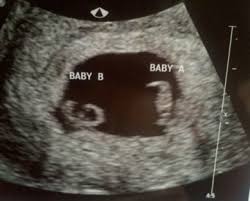

The exact time twins can be detected depends on the type of twins, for example, if they're identical (from one egg) or not. By eight weeks of your twin pregnancy, your babies will have buds for limbs that look like little paddles. Mehr als 200.000 maschinen sofort verfügbar. Most doctors will schedule an ultrasound somewhere between 6 and 10 weeks of pregnancy to confirm the pregnancy and check for multiples. Six full weeks is when you're 6+0 weeks pregnant. I should be 7 weeks, 4 days according to last period. (florida) i suspected i had twins because my beta numbers were high, i had two big follicles during my iui and i'm already big for less than 7 weeks! Seeing twins at 6 weeks is definitely possible. Besides ultrasound at 4 weeks, there are several changes during pregnancy for moms to expect. By four weeks, twins will start showing during ultrasound in form of 2 gestational sacs, but you cannot get clear indication of twins until 6 weeks. The first time i spotted but the other two were gushes. This was taken at 4 weeks 6 days. Some women would rather not know until both twins are relatively safe, while others want to know even if the chances of losing one twin are high.

We had the wonderful opportunity to see our baby's heart flickering on the screen!!! They said the doctor will call me and they may book an ultrasound in another two weeks. By four weeks, twins will start showing during ultrasound in form of 2 gestational sacs, but you cannot get clear indication of twins until 6 weeks. The ultrasound image is of twins at 4 weeks. No fetal heartbeat detectable at 5 weeks 6 days ultrasound.

4 weeks) between 5 ½ to 6 ½ weeks, a fetal pole or even a fetal heartbeat may be detected by vaginal ultrasound. We are first time parents and this is our first ultrasound. That's also called being 7 weeks pregnant. Besides ultrasound at 4 weeks, there are several changes during pregnancy for moms to expect. Transabdominal ultrasound cannot reliably diagnose pregnancies that are less than 6 weeks gestation. I'm brand new to this board. They said the doctor will call me and they may book an ultrasound in another two weeks. They said the baby looked small and measured about 6 weeks. Taken at 4 weeks, the ultrasound image shows a gestational sac. I didn't have a dating ultrasound because i knew my lmp and my midwife didn't see it as medically necessary, so i had my first ultrasound yesterday at 19 weeks, 6 days and we found twin boys. This was taken at 4 weeks 6 days. Ultra sound beim führenden marktplatz für gebrauchtmaschinen kaufen. Between 5 ½ to 6 ½ weeks, a fetal pole or even a fetal heartbeat may be detected by vaginal ultrasound.

Between 5 ½ to 6 ½ weeks, a fetal pole or even a fetal heartbeat may be detected by vaginal ultrasound. In this 7th week of pregnancy, your baby's lungs are starting to develop. The ultrasound picture above is of identical twins who share a placenta at 6+2 weeks. Beauty points sammeln & mit der douglas beauty card von exklusiven vorteilen profitieren. This begins with a small lung bud branching out from the upper part of the tube (esophagus) between your baby's mouth. Get to know what you need to take care of when 4 weeks and 6 days pregnant pregnant. I've been posting in october 2012 since i found out i was pregnant in february. You have approximately a 3.35 chance of having twins naturally , without the help of any fertility treatments. They said the baby looked small and measured about 6 weeks. 4 weeks) between 5 ½ to 6 ½ weeks, a fetal pole or even a fetal heartbeat may be detected by vaginal ultrasound. Little arms and legs sprout. You don't hear heartbeats any earlier or later with twins, that i know of. Mehr als 200.000 maschinen sofort verfügbar.